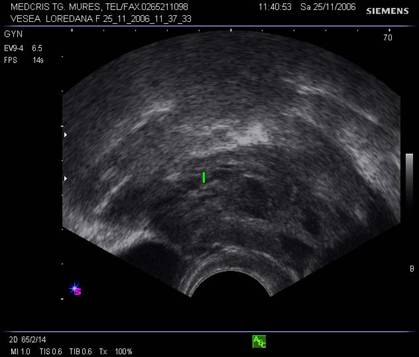

Endometrul - grosimea sa este apreciata in sectiune longitudinala. Masurarea se va face de la interfata miometru - endometru la interfata identica, opusa, de pe peretele celalat uterin. Maxim acceptat normal este de 1,5 cm in perioada de premenopauza.[5] Postmenopauza in mod normal nu depaseste 5 mm, de obicei este atrofic si apare ca o imagine ecogena lineara. Daca apare o colectie anecogena postmenopauzala intrauterina, prin atrofie cervicala, aceasta colectie nu trebuie sa fie masurata la calculul grosimii endometriale.[2,6]

Fig. nr.367. Uter in climax, linia cavitatii uterine discret neregulata si aparent fara endometru, datorita atrofiei